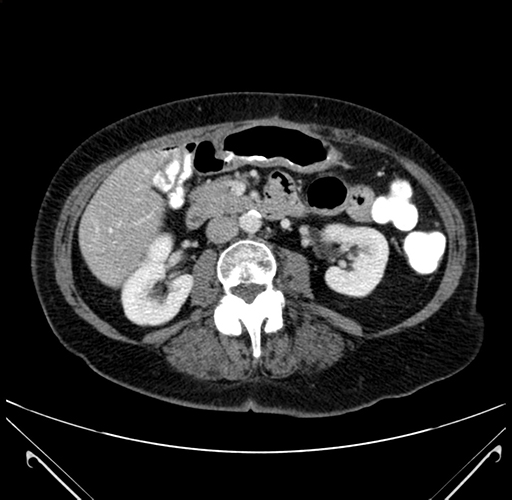

Pre-Chemo: Axial Venous